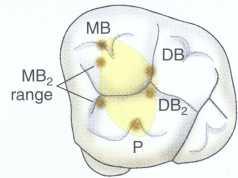

Treatment of maxillary molars is never routine (Figure 2-22). In a recent study of maxillary first and second molars an MB2 canal was found in 96% of the mesiobuccal roots of maxillary first molars and 94% of the maxillary second molars. Approximately 54% were located in the traditional access opening, 31% were found with the use of a bur, and 10% were found with the aid of a microscope. The MBZ canal orifice was found on average 1.82 mm lingual to the main MB canal orifice.9 In another study of the maxillary first molar using microscopy, the MB Z canal was located in

93% of first molars and 60% of second molars4 (Figures 2-23 and 2-24). The difficulty in access, high percentage of fourth and even fifth canals, and root curvatures put even the "routine" maxillary molar in a high-risk category.3 Complicating factors such as limited opening, crowns, changes in tooth angulation, tooth position, and calcification make predictable treatment of these teeth challenging for even the most experienced clinician trained in microscopy, ultrasonics, and rotary instrumentation.

FIGURE 2-24 The location of the MB 2 canal is mesial to the line connecting the MB and palatal orifice. In the maxillary first molar the MB2 canal is generally located within the range shown. In the maxillary second molar the location of the MB 2 s highly variable and can be located from the MB orifice to the palatal orifice (see Figs. 2-46 and 2-47).

Guidelines for canal location in the maxillary first molar (Figure 2-25) differ from that in the maxillary second molar. In the maxillary first molar the MB canal is located under the mesial buccal cusp (see Figure 2-25, D). The MBZ canal is located mesial to a line from the

MB canal toward the palatal canal (see Figures 2-25, E, and 2-26). The DB canal is located distal to the MB canal in the buccal groove area, slightly lingual to the MB canal (see Figure 2-25, G). The palatal canal is generally the largest canal and is located under the mesiolingual (ML) cusp (see Figure 2-25, F). These general locations remain the same as the pulp calcifies with age (Figure 2-27). Although these general principles apply to the maxillary second molar, the chamber may be narrower, resembling a straight line (see Fig. 2-55).